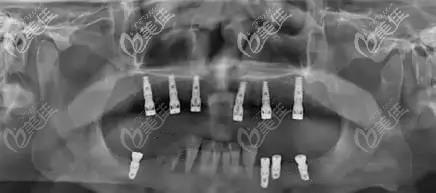

上颌即拔即种后的CT片▼